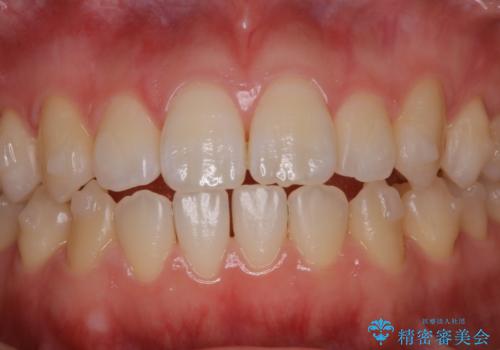

アタッチメント周囲のステインOFFをPMTC で

- インビザライン矯正治療中に、アタッチメント周囲のステインが気になるとのことでした。PMTC30分コースを行いました。

マウスピース矯正インビザライン治療では、歯の表面にアタッチメントという突起を設定します。(アタッチメントは歯の動きを効率的に移動するためのものです)

アタッチメントが歯に付くと、表面が凸凹し磨き残しが多くなったりと、プラークや歯石・着色がつきやすくなることがあります。